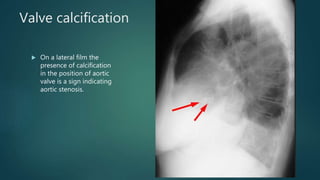

Valve calcification

 On a lateral film the

presence of calcification

in the position of aortic

valve is a sign indicating

aortic stenosis.